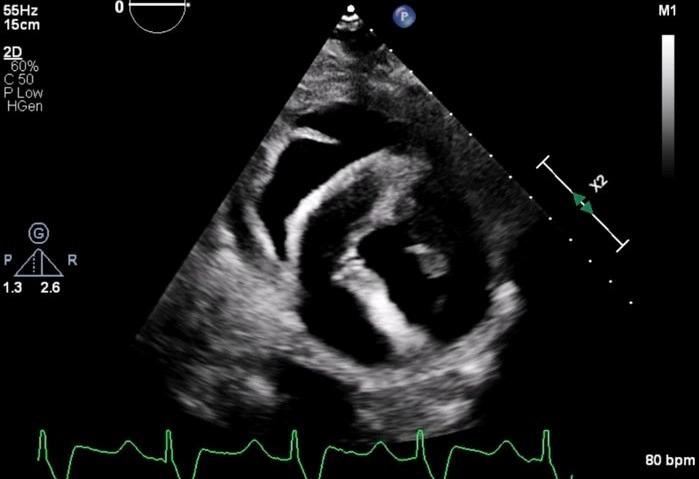

Hình ảnh siêu âm quả tim lợn sau khi cấy ghép vào người ông Bennett. Ảnh: The New England Journal of Medicine 2022.